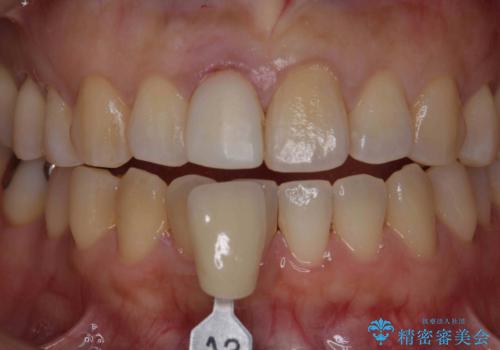

オーダーメイドで造る、自然な前歯セラミッククラウン

精密な仮歯をいれ、歯周組織を整えるとともにファイバーコア築盛、シェードテイキングを行い見た目に自然なジルコニアクラウンを製作していきます。

ジルコニアクラウンの中でも当法人のグレードの高い、スペシャル・エクセレントプランはオーダーメイドで色調を合わせることで周囲の歯に馴染んだ自然な歯を製作することのできるプランです。